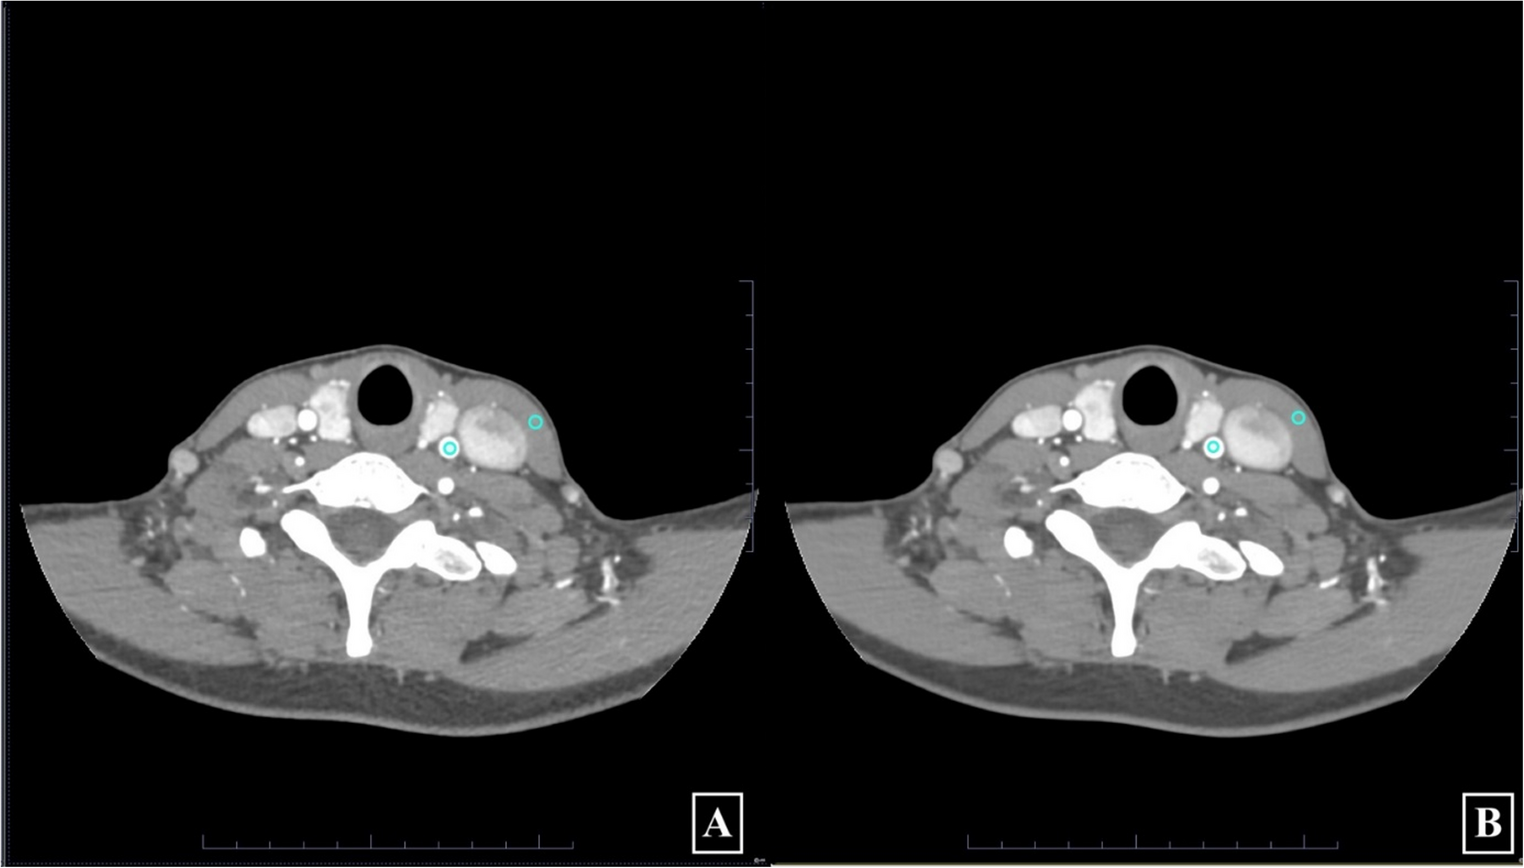

Improved CTA imaging for stroke evaluation – deep learning and iterative reconstruction comparative study

This study compares a novel reconstruction algorithm deep learning-based image reconstruction (DLIR) and adaptive statisti...